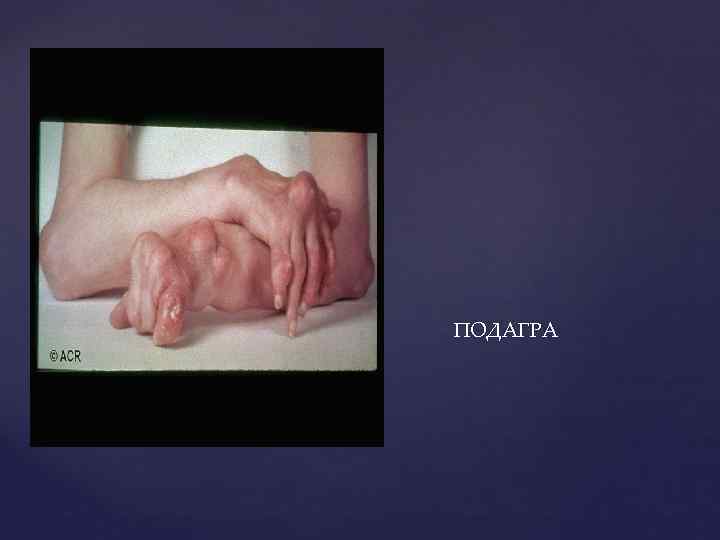

ПОДАГРА

ПОДАГРА

ПОДАГРА – это системное тофусное заболевание, развивающиеся в связи с воспалением в месте отложения кристаллов моноурата натрия или мочевой кислоты у людей с гиперурикемией, обусловленной внешнесредовыми и/или генетическими факторами

ПОДАГРА – это системное тофусное заболевание, развивающиеся в связи с воспалением в месте отложения кристаллов моноурата натрия или мочевой кислоты у людей с гиперурикемией, обусловленной внешнесредовыми и/или генетическими факторами